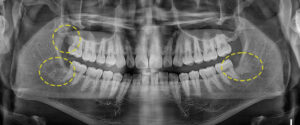

마지막으로 소개해 드릴 환자분은

상, 하, 좌, 우 4개의 사랑니를 모두

가지고 계신 분이었는데요.

교정을 끝내고 사랑니로 인해

추후 치열이 변형될 수 있어

예방 차 사랑니발치를 하러 내원해 주셨어요.

사랑니들 중 특히 하악 우측 사랑니는

완전 수평 매복 되어 있고, 신경관과도

매우 가까우며 치아의 뿌리가

항아리 모양처럼 휘어져 발치의 난이도가

매우 높은 편이었는데요..

우측 상,하악 먼저 발치를 진행하기로 하였으며,

다행히 인접한 치아나 신경관에 손상 없이

홍은동사랑니발치를 진행하였어요.👍

약 2주 후 왼쪽 상, 하악 발치를 진행하였고

오른쪽에 비해 수월하게 발치되었어요.